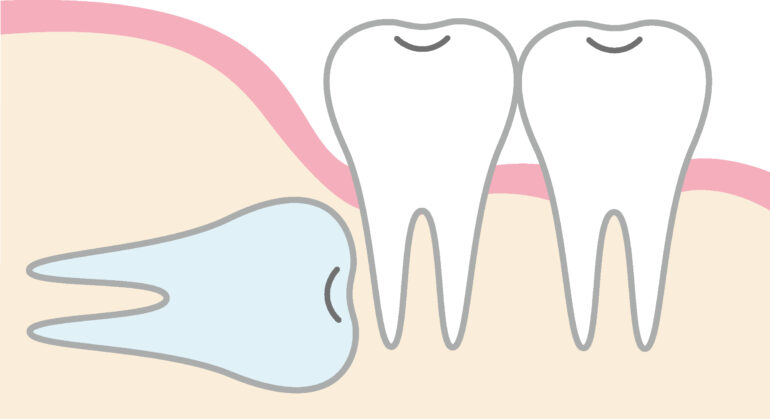

歯ぐきの中に完全に埋まってしまっていて表面には出ていない、見えない状態です。親知らずがある部分が腫れている、痛みがある、他の歯や顎関節への影響がある場合は抜歯を検討する必要があります。水平埋伏智歯

親知らずが横向きに生えている状態です。横向きに生えているために歯を圧迫して歯並びに影響を与えたり、歯茎などの腫れや痛みの原因になることがあります。年齢を重ねたり、歯磨きがきちんとできていないとより症状が出やすくなるので、早めに抜歯をすることをお勧めしています。

親知らずが横向きに生えている状態です。横向きに生えているために歯を圧迫して歯並びに影響を与えたり、歯茎などの腫れや痛みの原因になることがあります。年齢を重ねたり、歯磨きがきちんとできていないとより症状が出やすくなるので、早めに抜歯をすることをお勧めしています。半埋伏智歯

2. 親知らずが手前の歯を強く押して、歯並びに悪い影響を与えている場合

親知らずが横向きや斜めに生えている場合、隣の歯(第二大臼歯)に強い圧力をかけることがあります。この圧力によって、手前の歯が移動して歯並びが乱れたり、噛み合わせが悪くなることがあります。また、歯の詰まりが生じると、隣接する歯との間に食べかすが溜まりやすくなり、結果的に虫歯や歯周病の原因となるため、抜歯が推奨されるケースです。